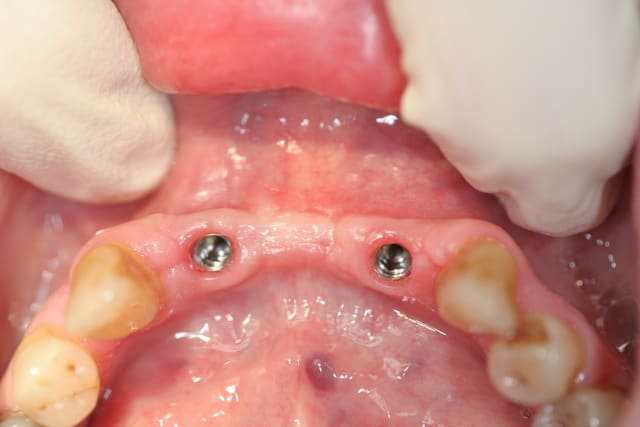

Là, ton truc sur implants, c'est bien de voir quelques choses de différents !

T'aurais pas du placer les implants si lingual !

;-))

C'est drôle, j'ai fais un truc du genre hier (plus simple)